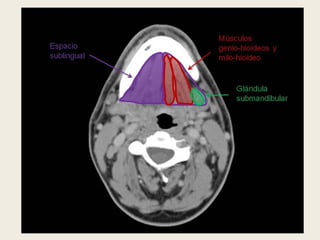

ESPACIO PAROTÍDEO.

 Localizado lateralmente al espacio parafaríngeo y

delimitado por la capa superficial de la fascia cervical

profunda. En muchas ocasiones comunica libremente con

el espacio parafaríngeo preestiloideo por ausencia de

fascia entre ambos espacios. Contiene la glándula

parótida, la porción intraparotídea del nervio facial,

ganglios intraglandulares, arterias carótida externa y

maxilar interna, y vena retromandibular.

 Una lesión maligna puede tener diseminación perineural

hacia el hueso temporal a través del nervio facial.